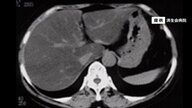

「肝臓」脂肪が急増…コロナ禍の運動不足も原因?放置すればがんの恐れも 予防法をご紹介【福井発】

ライフ

2022年5月15日